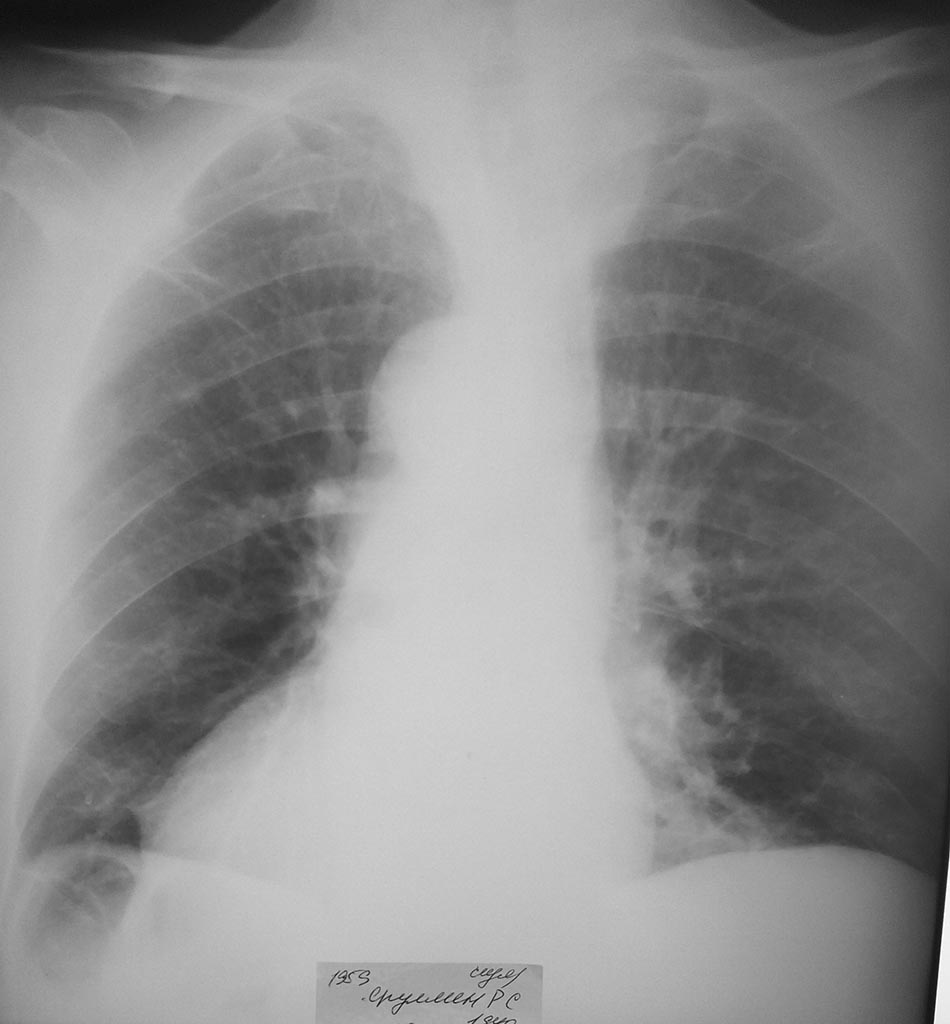

после операции

гемоглабин 63